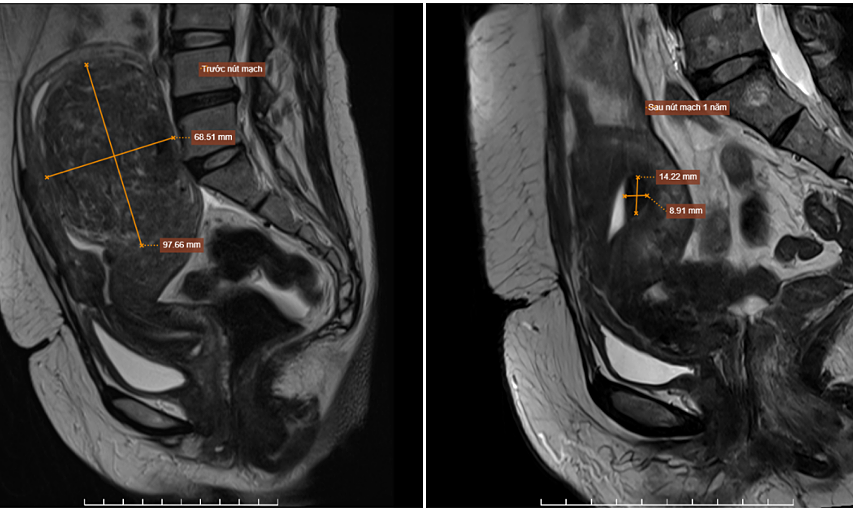

Hai năm trước, chị Lan phát hiện khối u xơ tử cung khoảng 4 cm nhưng không điều trị. Nay rối loạn kinh nguyệt kéo dài, chị đến Bệnh viện Đa khoa Tâm Anh Hà Nội chụp MRI cho thấy u xơ tăng lên tới 9,7×6,8 cm nằm trong lớp cơ tử cung, thành sau đáy tử cung, đẩy lồi niêm mạc tử cung. Bác sĩ chẩn đoán u có thể tăng sinh mạch mạnh, thuộc nhóm FIGO 2 – dễ gây rong kinh và đau bụng dữ dội khi hành kinh.

Ảnh khối u của chị Lan thay đổi kích thước trước và sau khi can thiệp. Ảnh: Bệnh viện Đa khoa Tâm Anh